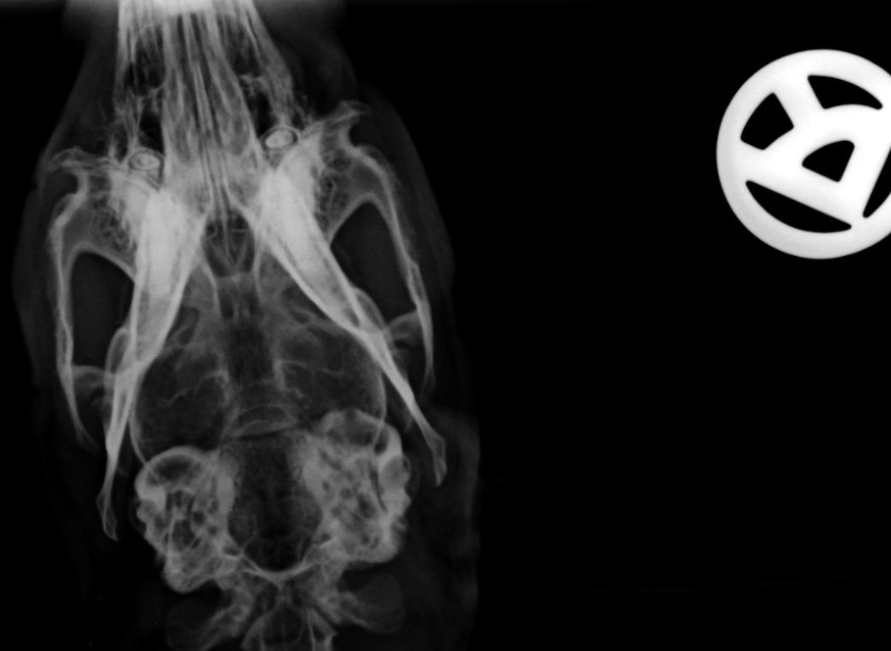

Falls ein Röntgenbild des Kopfes erstellt wird, sind bei einer Otitis media ggf. Verschattungen oder Asymmetrien im Bereich der knöchernen Strukturen des Mittelohres zu sehen.

mit knöcherner Zusammenhangstrennung der Bulla (erste lytische Anzeichen auf Perforation)

Sieht man im Röntgen Veränderungen, dann sind sie in der Regel schon recht weit fortgeschritten und der Knochen bereits angegriffen. Für die Beurteilung des Trommelfells, Sekretansammlungen und der feinen Strukturen des Innenohres ist ein Röntgenbild nicht aussagekräftig genug. Sieht man daher keine Auffälligkeiten im Röntgen, ist es leider keine Garantie für gesunde Ohren.

Der Goldstandard der Ohrdiagnostik bei Verdacht auf Otitis media/interna und die sensitivste Methode ist die Computertomographie. Hiermit können die äußeren Gehörgänge, inneren Strukturen und deren Füllungsstand genau beurteilt werden. Bei einem Wach-CT ist auch keine Narkose nötig und es ist eine sehr schnelle und für die Tiere vergleichsweise stressfreie Methode.

Die Vergleichsstudie von Reuschel (2018) zeigt, dass bei fast 2/3 der Fälle keine Veränderungen im Röntgen, jedoch im CT zu sehen sind. Ein CT ist daher die sicherste Diagnostik. Auch eine Untersuchung mittels digitaler Volumentomographie (DVT) ist zur Diagnostik geeignet und sogar noch genauer als ein CT.